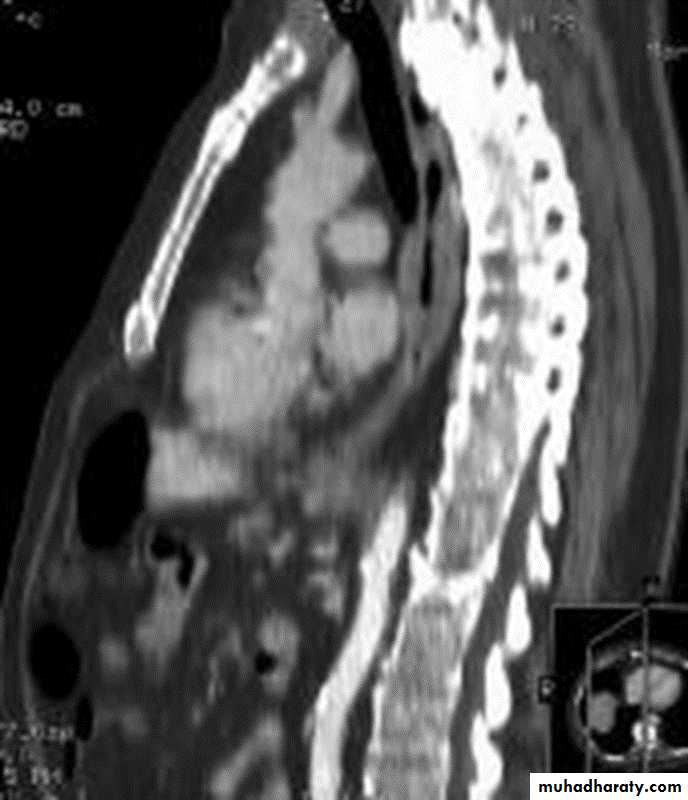

Computed Tomography

Contrast-enhanced CT plays an important role in the1.staging of esophageal carcinoma.

2.determining the extent of the local tumor

3.invasion of mediastinal structures

4.involvement of supra clavicular, mediastinal, or upper abdominal lymph nodes

5. Assessment of the distant metastases

examination should extend from the thoracic inlet through the liver

CT essential in the Dx & staging of the CA

CT finding of esophageal malignancy

1.Eccentric or circumferential wall thickening is greater than 5 mm.

2.Peri-esophageal soft tissue and fat stranding may be demonstrated.

3.A dilated fluid- and debris-filled esophageal lumen is proximal to an obstructing lesion.

4.Aortic invasion .

5.Osophageal CA is often metastatic at the time of presentation ( look for the LN & distal metastasis ) .